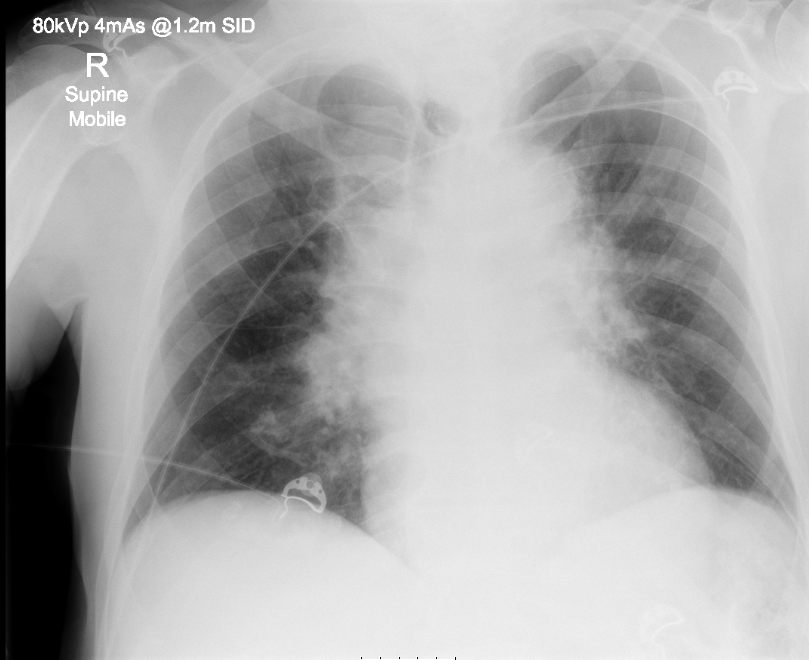

There would have been little evidence beyond history to strongly suggest the correct diagnosis in the ED. The textbook finding of Beck’s triad in cardiac tamponade was not useful as the patient did not have distended neck veins, and the presence of “muffled heart sounds” is not a reliable finding in a noisy ED. Without POCUS the patient would likely have waited for a 12-lead ECG and a CXR to be obtained prior to CT being requested, a delay of at least 10 minutes in this time-critical case.